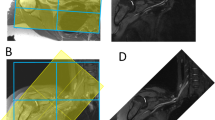

Detailed knowledge of the brachial plexus anatomy is essential not only to surgeons managing brachial plexus injuries [3] but also to anesthetists performing brachial plexus block [4]. Regional anesthesia with brachial plexus block is widely used as an adjunct or alternative to general anesthesia during upper limb surgery [5,6,7,8]. However, most peripheral nerve blocks are performed by a limited number of specialists, which reflects the challenges and complexities of these procedures [9]. The success rate of ultrasound-guided brachial plexus block is 77–94% [9, This prospective study included patients who underwent ultrasound-guided brachial plexus block in the Anesthesiology Department of Bei**g Jishuitan Hospital (Bei**g, China) between October 2019 and June 2022. The inclusion criteria were as follows: (1) aged 18–65 years-old; (2) scheduled to receive ultrasound-guided brachial plexus block as anesthesia for orthopedic surgery, anesthesia for closed fracture reduction, or pain therapy; (3) American Society of Anesthesiologists (ASA) physical status classification stage I–III; and (4) volunteered to participate in this study. The exclusion criteria were: (1) incapable of cooperating with the study protocol or maintaining the required position for imaging; (2) brachial plexus dysfunction; (3) previous surgery to the nerve segment to be scanned; (4) wound or infection of the neck or at the interscalene level; and (5) allergic to the ultrasonic coupling agent. The study was approved by the Ethics Committee of Bei**g Jishuitan Hospital (approval no. 202104-14), and all patients provided informed written consent. The following baseline demographic and clinical characteristics were obtained: age, sex, height and body weight. The patient was placed in the supine position with their head slightly turned to the contralateral side. A high-frequency probe was used, and the medial side was displayed on the right-hand side of the image. After pre-scanning of the image acquisition area to optimize the ultrasound parameters, continuous scanning was performed from the supraclavicular area (start point) to the level of the transverse process of C5 (end point). The probe was fine-tuned to optimize the image before it was acquired, and the probe was maintained in a stable position for 1 s before and after the button was pressed for image acquisition. A cross-sectional image was acquired at the supraclavicular region, at the region between the supraclavicular region and the level of the transverse process of C7, and at the level of the transverse process of C7 (Fig. 1). Ultrasound images acquired at various levels. (A) Images acquired at the supraclavicular region. The area containing nerves (and including as many nerves as possible) but excluding the middle scalene muscle was marked (N, right-hand images). The subclavian artery was also marked (SA). (B) Images acquired at a region between the supraclavicular area and the level of the transverse process of C7. The area containing all the nerves (C5–C7 as well as C8 if it was clearly visible on the surface of the first rib) was marked (N). (C) Images acquired at the level of the transverse process of C7. The area containing the nerves (C5 and C6 plus C7 if the surface of the transverse process of C7 was clearly displayed) was marked (N) For quality testing, 10% of the images were randomly selected after acquisition or marking. The images were reviewed by three physicians, each of which had at least 5 years of experience in clinical practice. Images with the essential structures displayed and marked relatively precisely were considered to be of high quality; the criteria used to define a poor quality image are shown in Supplementary Table 1. An image was defined as being of high quality if two of the three reviewers classified it as high quality (i.e., not poor quality). The principle used for brachial plexus extraction mimicked the process of brachial plexus recognition by human physicians. The process consisted of multiple convolution and pooling layers to detect local features followed by fully connected layers, with the softmax function used in the final layer prior to output (Supplementary Figure S1). A large number of high-quality images were input into the pool in different batches for computer learning and recognition.And a Unet model was used for segregation. The results of the recognition process were then validated. This study evaluates the accuracy of image separation by calculating the S ø rensen Dice coefficient (Dice index) and Jaccard index, both of which are statistics that estimate the similarity between two samples and are used in image segmentation to compare algorithm output against a reference mask. The Dice index and Jaccard index were determined according to the degree of overlap between the segmentation predicted by the CNN and the ground truth segmentation manually drawn by the physicians. The Dice index was calculated as (2 × area of the overlap between the predicted segmentation and the ground truth segmentation) / (area of the predicted segmentation + area of the ground truth segmentation) (Fig. 2A). The Dice index had a value of 0–1, and a value ≥ 0.75 was taken to indicate good overlap between the predicted and ground truth segmentations, i.e., good segregation by the CNN. The Jaccard index was calculated as (area of the overlap between the predicted segmentation and ground truth segmentation) / (area of the region formed by merger of the predicted segmentation and ground truth segmentation) (Fig. 2B). A Jaccard value > 0.5 was taken to indicate a good overlap. SPSS Statistics 27.0 software (IBM Corp., Armonk, NY, USA) was used for the analysis. Normally distributed quantitative data are described as the mean ± standard deviation. Non-normally distributed quantitative data are presented as the median (range). Qualitative data are described as frequency (constituent ratio or percentage). The final analysis included 502 images from 127 patients aged 41 ± 14 years-old (72 men, 56.7%). The mean height and mean body weight of the participants was 168.10 ± 8.29 cm and 67.65 ± 13.13 kg, respectively (Table 1). The neural and vascular structures in ultrasound images can be recognized after training using the Unet semantic segmentation model (Fig. 1). In this model, we collected ultrasound images of the intermuscular sulcus area, and it can be seen that the brachial plexus nerves in different positions of the intermuscular sulcus are well recognized (Fig. 1S). The mean Dice index of the CNN for segregation of the brachial plexus at the interscalene level was 0.748 ± 0.190, which was extremely close to the threshold level of 0.75 for good overlap between the predicted and ground truth segregations (Table 2). Furthermore, the Jaccard index was 0.630 ± 0.213, which exceeded the threshold value of 0.5 for a good overlap (Table 2). The Dice index was mainly distributed around a value of 0.8, while the Jaccard index was mainly distributed around a value of 0.6 (Fig. 3). Distribution of the Dice index and Jaccard index. Each circle is color-coded according to the number of number of segmentations with a particular Dice Index and Jaccard index. The color represents the frequency of occurrence and the darker the color, the more IOU and DICE appear. IOU: Jaccard index (also known as the Intersection-Over-Union). The main finding of this study was that the developed CNN was able to segregate the brachial plexus in ultrasound images obtained at the interscalene level with a mean Dice index of 0.748 and a mean Jaccard index of 0.630. These results indicate that the CNN established in this study performed well in the segregation of the brachial plexus at the interscalene level. We anticipate that, after further development, the CNN could be used to train ultrasonographers and anesthetists to recognize the brachial plexus and to facilitate the identification of the brachial plexus of a patient in real-time during ultrasound-guided interscalene block. An interscalene block is generally performed on patients undergoing surgery of the shoulder, upper arm or elbow but is not recommended for hand operations because it tends to spare the inferior trunk [15]. However, incorrect needle placement can result in complications such as pneumothorax, nerve injury, epidural or intrathecal injection of local anesthetic, spinal cord trauma, shortness of breath due to unintended phrenic nerve block, and Horner syndrome due to unintended cervical plexus block [16]. The present study developed a SegNet semantic segmentation model to train the CNN to identify the brachial plexus features in ultrasound images, so that it learned to automatically segregate the brachial plexus in ultrasound images obtained at the interscalene level. Notably, the CNN algorithm performed well in the segregation of the brachial plexus at the interscalene level, as evidenced by a Dice index of 0.748 (very close to the threshold level of 0.75 for a good overlap with the ground truth segmentation) and a Jaccard index of 0.630 (which exceeded the threshold of 0.5 for a good overlap). The performance of our CNN compares well with that of algorithms for brachial plexus segregation reported by other studies. Liu et al. developed a deep adversarial network comprising a segmentation network and discriminator network, and the Jaccard index for brachial plexus segmentation was 0.693 without elastic transformation and 0.733 with elastic transformation [17]. Moreover, the authors reported that the Jaccard values for their deep adversarial network were numerically higher than those reported previously for a support vector machine and conditional random fields model (0.454) [18], a fully convolutional network (0.572) [19], a CNN incorporating a conditional random field (0.693) [20], piecewise training of conditional random fields with CNN pairwise potentials (0.716) [21], and a recurrent convolutional neural network (0.721) [22]. Wang et al. used preprocessing and a modified U-Net architecture to generate a model that segregated the brachial plexus with a Dice index of 0.709 [23]. Additionally, a deep learning model described by Yang et al. was able to locate the interscalene brachial plexus in ultrasound images more accurately than nonexperts, as evidenced by the distance between the lateral midpoints of the nerve sheath contours of the model predictions and the ground truth (0.8 mm for the model and 3.4 mm for non-experts, P < 0.001) [24]. This study has some limitations. First, the CNN was designed for brachial plexus segmentation at the interscalene level, so it remains to be determined whether the algorithm would also be capable of brachial plexus segmentation at the supraclavicular, infraclavicular and axillary levels. Second, only the brachial plexus was targeted, hence it was not established whether the CNN could be used for segmentation of other peripheral nerves. Third, patients with brachial plexus dysfunction were excluded, so further research is required to evaluate whether the algorithm would be suitable for use in patients with brachial plexus dysfunction or anatomic abnormalities. Fourth, the study only included a training set and did not utilize a validation set. Additional studies are merited to further develop and validate the CNN described in this study. In conclusion, this study describes an efficient CNN that exhibited good performance in the segmentation of the brachial plexus at the interscalene level, with a Dice index of 0.748 and a Jaccard index of 0.630. We anticipate that this CNN could be developed into a useful tool to train clinicians to recognize the brachial plexus in ultrasound images and to assist anesthetists performing brachial plexus block.Methods